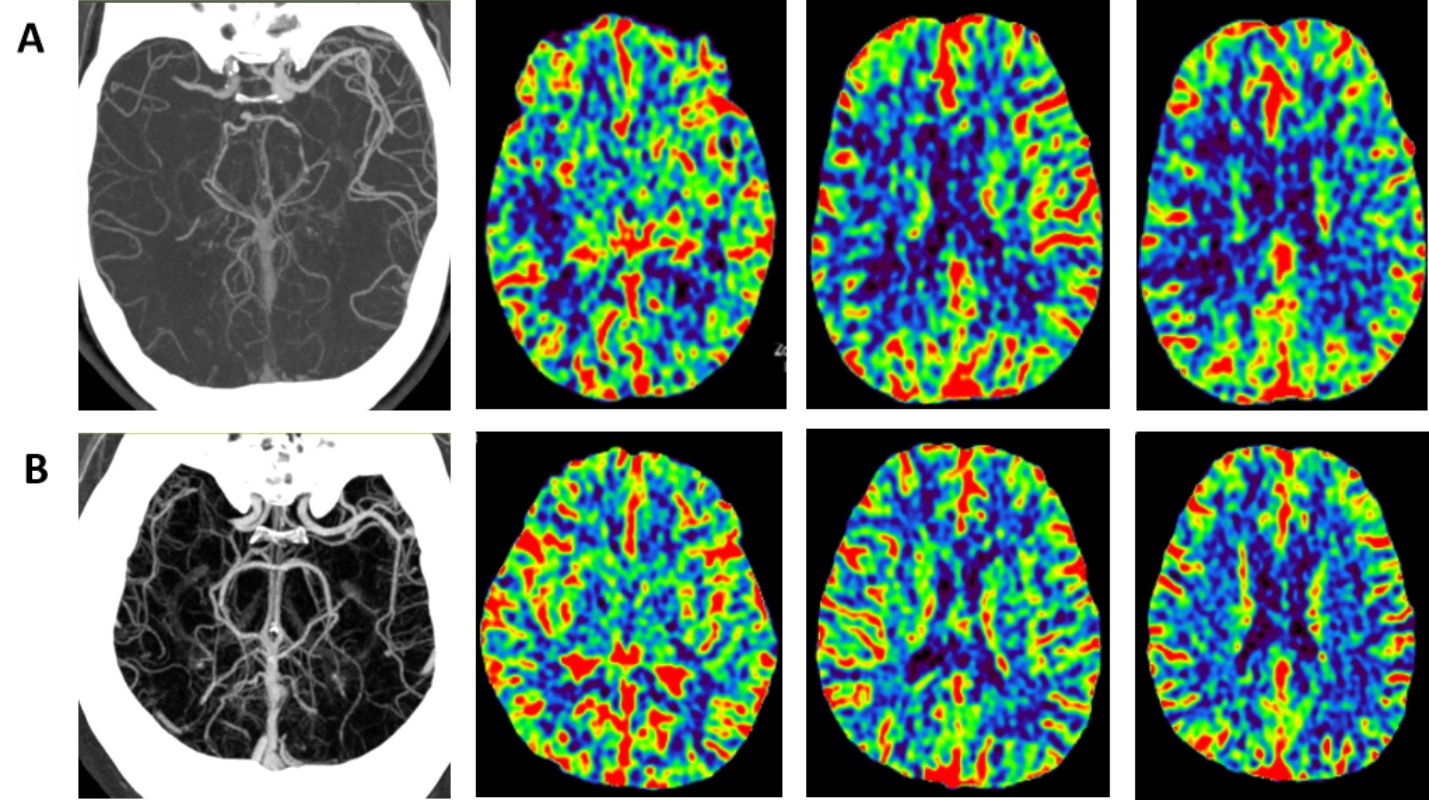

3.3. 典型病例研究血管闭塞部位、灌注模式与临床结局的关系

为了研究CTA与CTP在不同预后情况的AIS患者中的影像特征,我们收集了几例具有特征性影像表现与不同预后的AIS患者临床影像信息,逐一分析显示:图1中,患者A的CTA证实存在大脑中动脉M1段远端闭塞(CTA-APCIIS评分6分),且CTP显示CBV较对侧明显降低(CTP-ASPECTS评分0分),提示核心梗死区已形成。患者临床神经功能缺损严重(NIHSS评分高),后续血管再通治疗效果有限,90天随访改良Rankin量表(mRS)评分为4分,预后不良。患者B中尽管CTA显示大脑中动脉M1段近端严重闭塞(CTA-APCIIS评分8分),但CTP未显示明确的灌注缺损,尤其是CBV较对侧基本对称(CTP-ASPECTS评分10分) (见图1)。这表明患者通过良好的软脑膜侧支循环等代偿机制,有效地维持了缺血区域的灌注,可能保留了较大的缺血半暗带。患者接受了紧急血管内取栓治疗并实现成功再通,神经功能迅速改善,90天mRS评分为1分,预后良好。

图注:患者A的CTA示右侧大脑中动脉M1段远端及其以远分支血管未见显影,提示该血管节段存在闭塞;CTP示右侧额顶叶皮层及皮层下区域可见明确的灌注异常,表现为该区域脑血容量(CBV)较对称显著降低,CTA-APCIIS评分6分,CTP-ASPECTS评分0分。患者B的CTA示右侧大脑中动脉M1段近端完全闭塞;CTP示右侧大脑半球CBV与健侧对比未见显著差异,CTA-APCIIS评分8分,CTP-ASPECTS评分10分。

Figure 1. Representative case illustrates the relationship between vessel occlusion site, perfusion pattern, and clinical outcome

1. 代表性病例体现血管闭塞部位、灌注模式与临床结局的关系